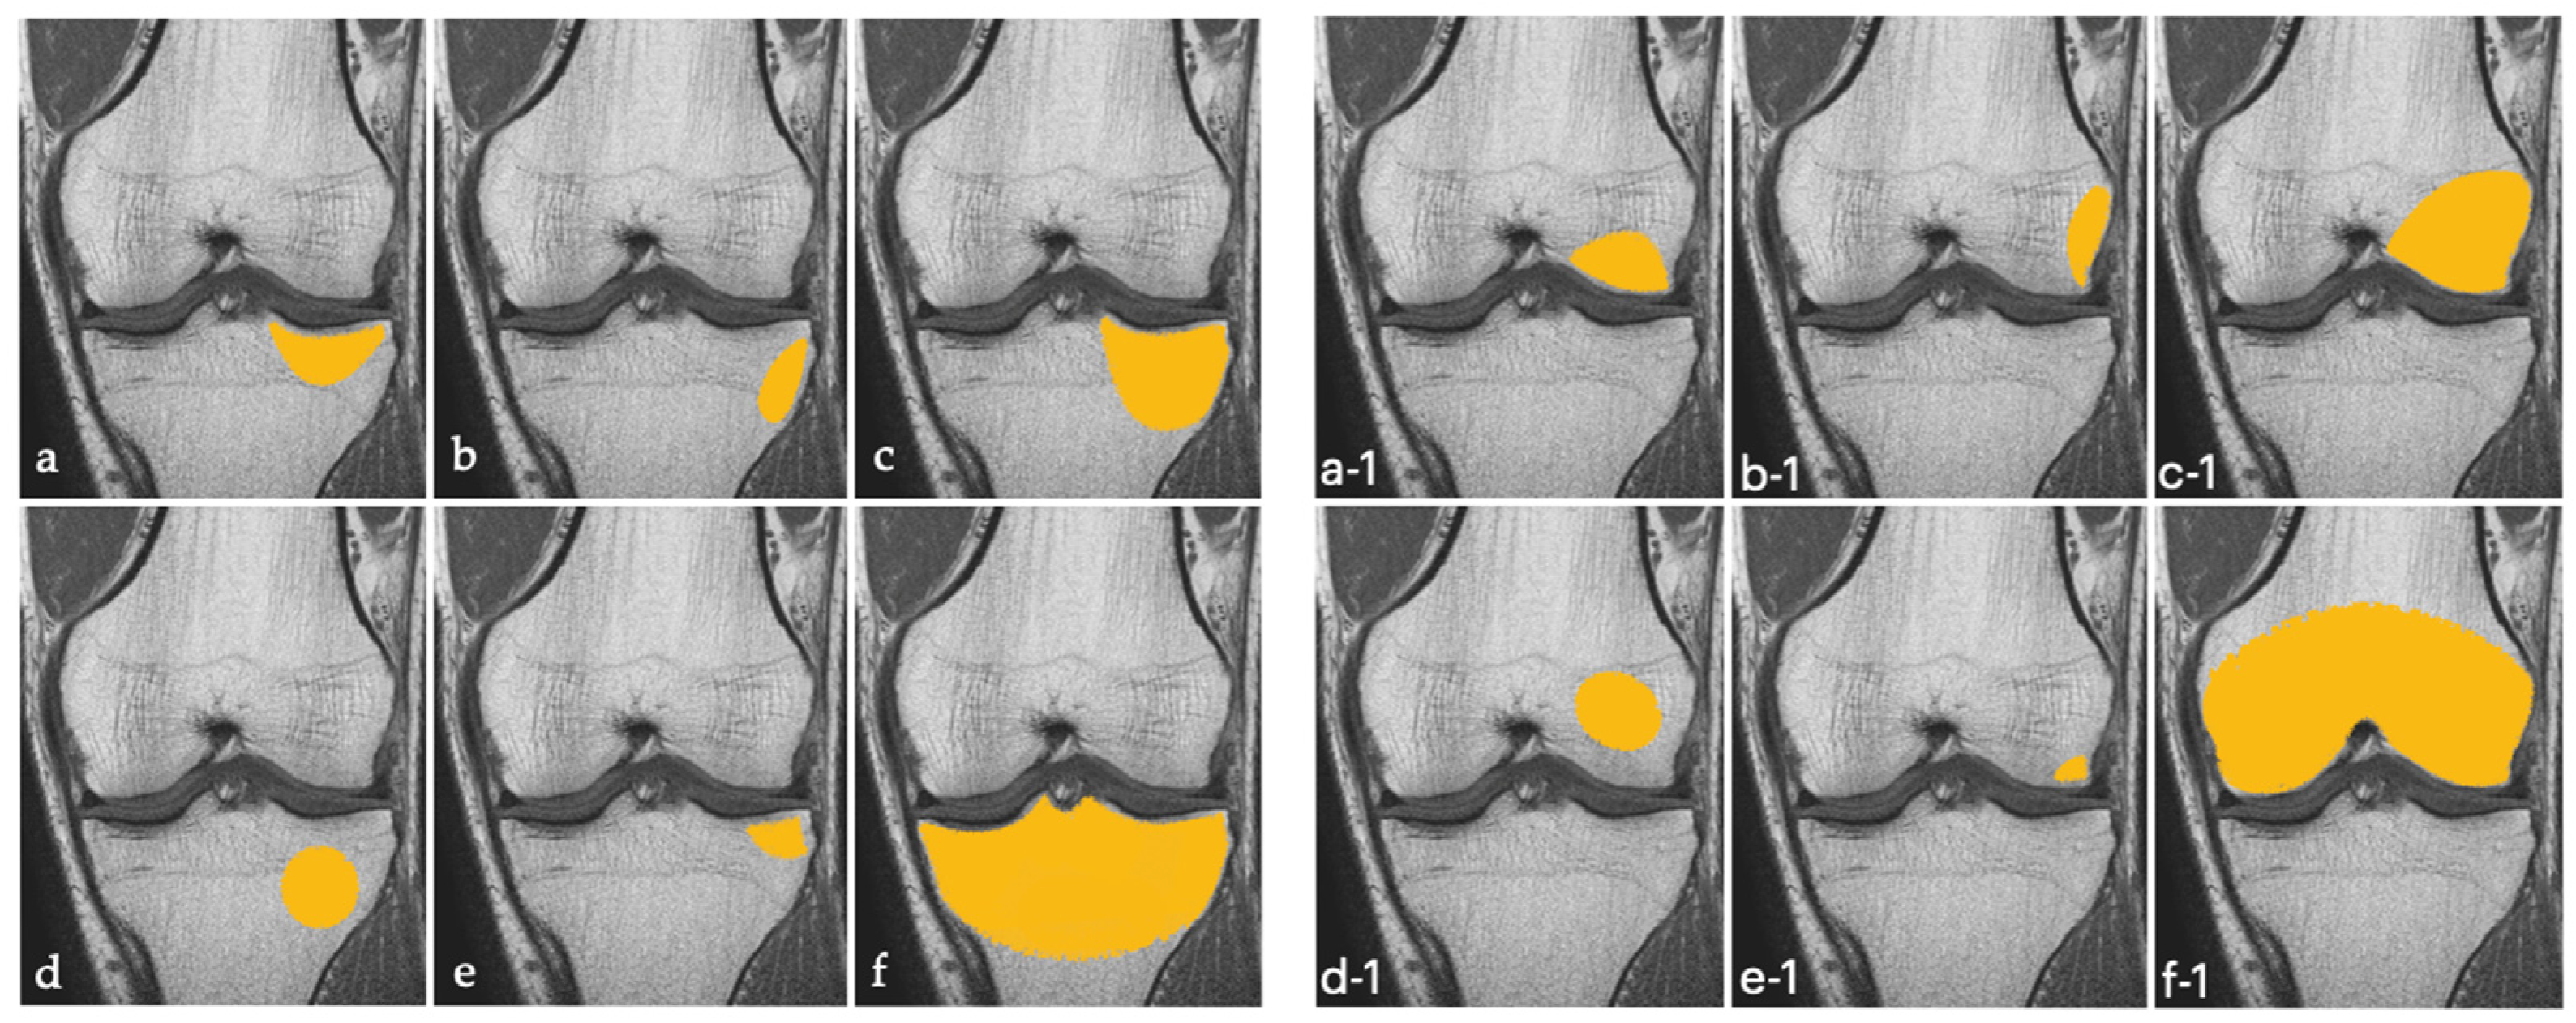

We defined BME of the knee according to the topographic classification proposed by Compagnoni et al., well-illustrated in Figure 2 below [18].

Figure 2.

Schematic illustration of tibial (on the left (a–f)) and femoral (on the right (a-1–f-1)) primary bone marrow edema of the knee, in according to Compagnoni’s classification [18].

Of 5352 patients who were referred to our clinic from 1 January 2015 to 31 August 2021, 330 were diagnosed with BME of the knee and 48 had primary BME of the knee (Figure 3). All had complete bone marrow lesions on MRI, i.e., lesions involving the articular and medial or lateral cortex of the condyle that exceeded 50% of the medial or articular surface or crossed the physis [18].

There was no side predominance in the painful knee. All patients had complete (type C) lesions [18] that involved the medial tibial plateau (43.8%), the lateral tibial plateau (6.2%), the medial femoral condyle (31.2%), or the lateral femoral condyle (18.8%).

All our patients had complete (type C) bone marrow lesions according to Compagnoni et al. [18]. It may therefore be hypothesized that type C primary lesions are more likely to regress with conservative treatment.